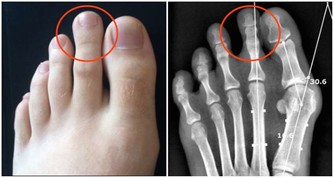

浸漬糜爛型:足部糜爛發白,常長在趾縫,特別是3、4及4、5腳趾縫間;